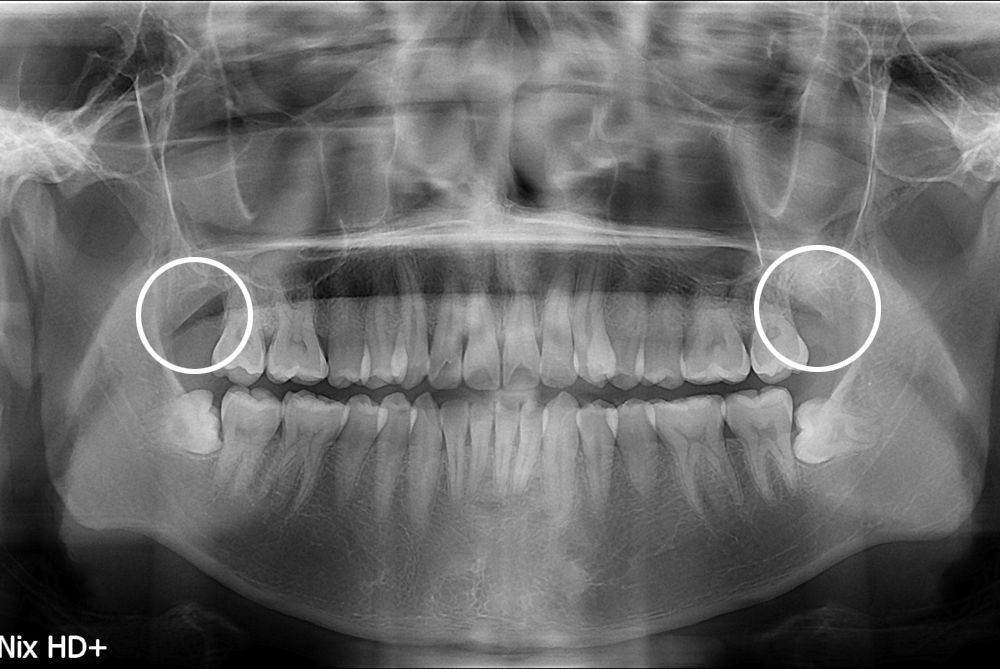

치료후 : 2017-10-20

세종치과는 구강악안면외과학 박사이신 원장님이 발치하는 치과입니다.